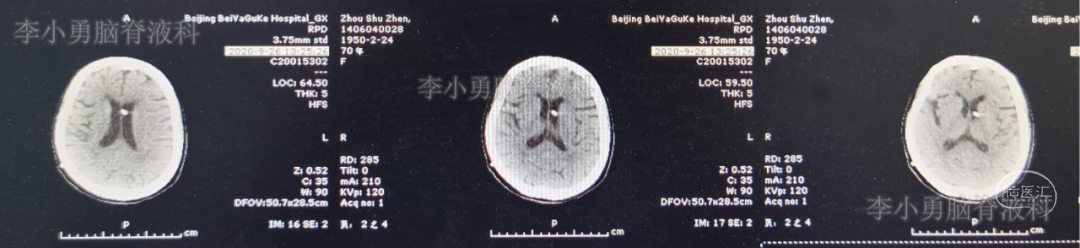

2020年5月10日(即第一次颈椎术后18天)患者洗脸时再次突发头晕,表现为天旋地转,恶心,呕吐视物旋转,行走不稳,经休息症状不缓解,再次就诊入院。查头颅MR显示急性小脑梗塞(图-3),给予改善微循环、降血脂、控制血压及对症治疗后患者头晕好转出院,但行走时仍有摇晃感。

图-3:2020年5月10日头颅MR

2020年7月14日(即第一次颈椎病术后83天)患者又出现头晕加重,尤以低头扭头时明显(注:患者未按照医嘱佩戴颈托),而且双上肢放射痛,麻木再次出现,双下肢无力,行走不稳,门诊复查头颅MR示小脑陈旧性梗塞(图-4)。

图-4:2020年7月14日头颅MR